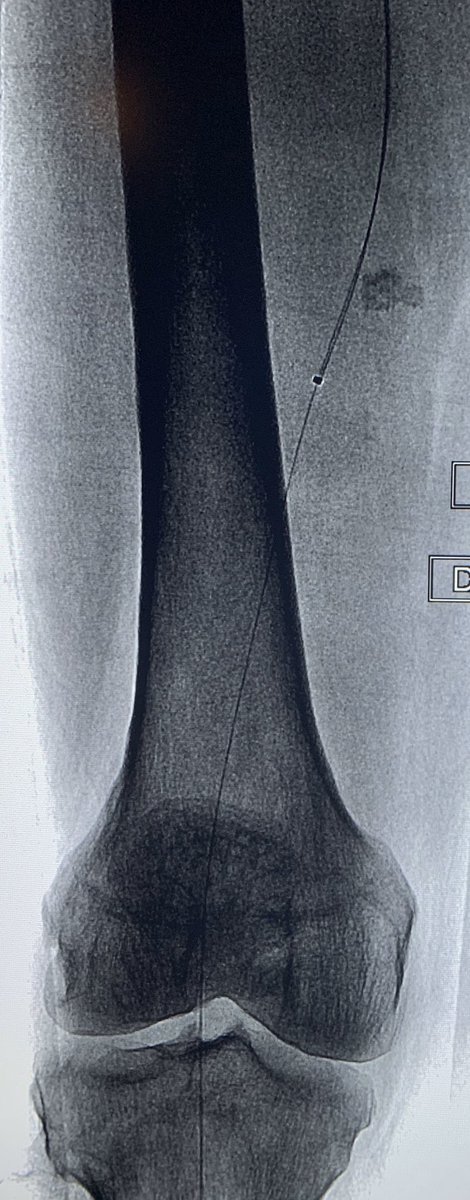

Eccentric

#softplaque of#SFA treated with#Laser#turbopower in a#claudicant. Helps#wirebias.#irad@SIRspecialists@SIRRFS@SIR_ECS#atherectomy#angioplasty#PAD@CLIVascular@ISETNews@AMPSymposium@PhilipsHealth@EVToday@JVIRmedia#claudication@CLI_Global@CLIfighterspic.twitter.com/Qh88bTx0kA